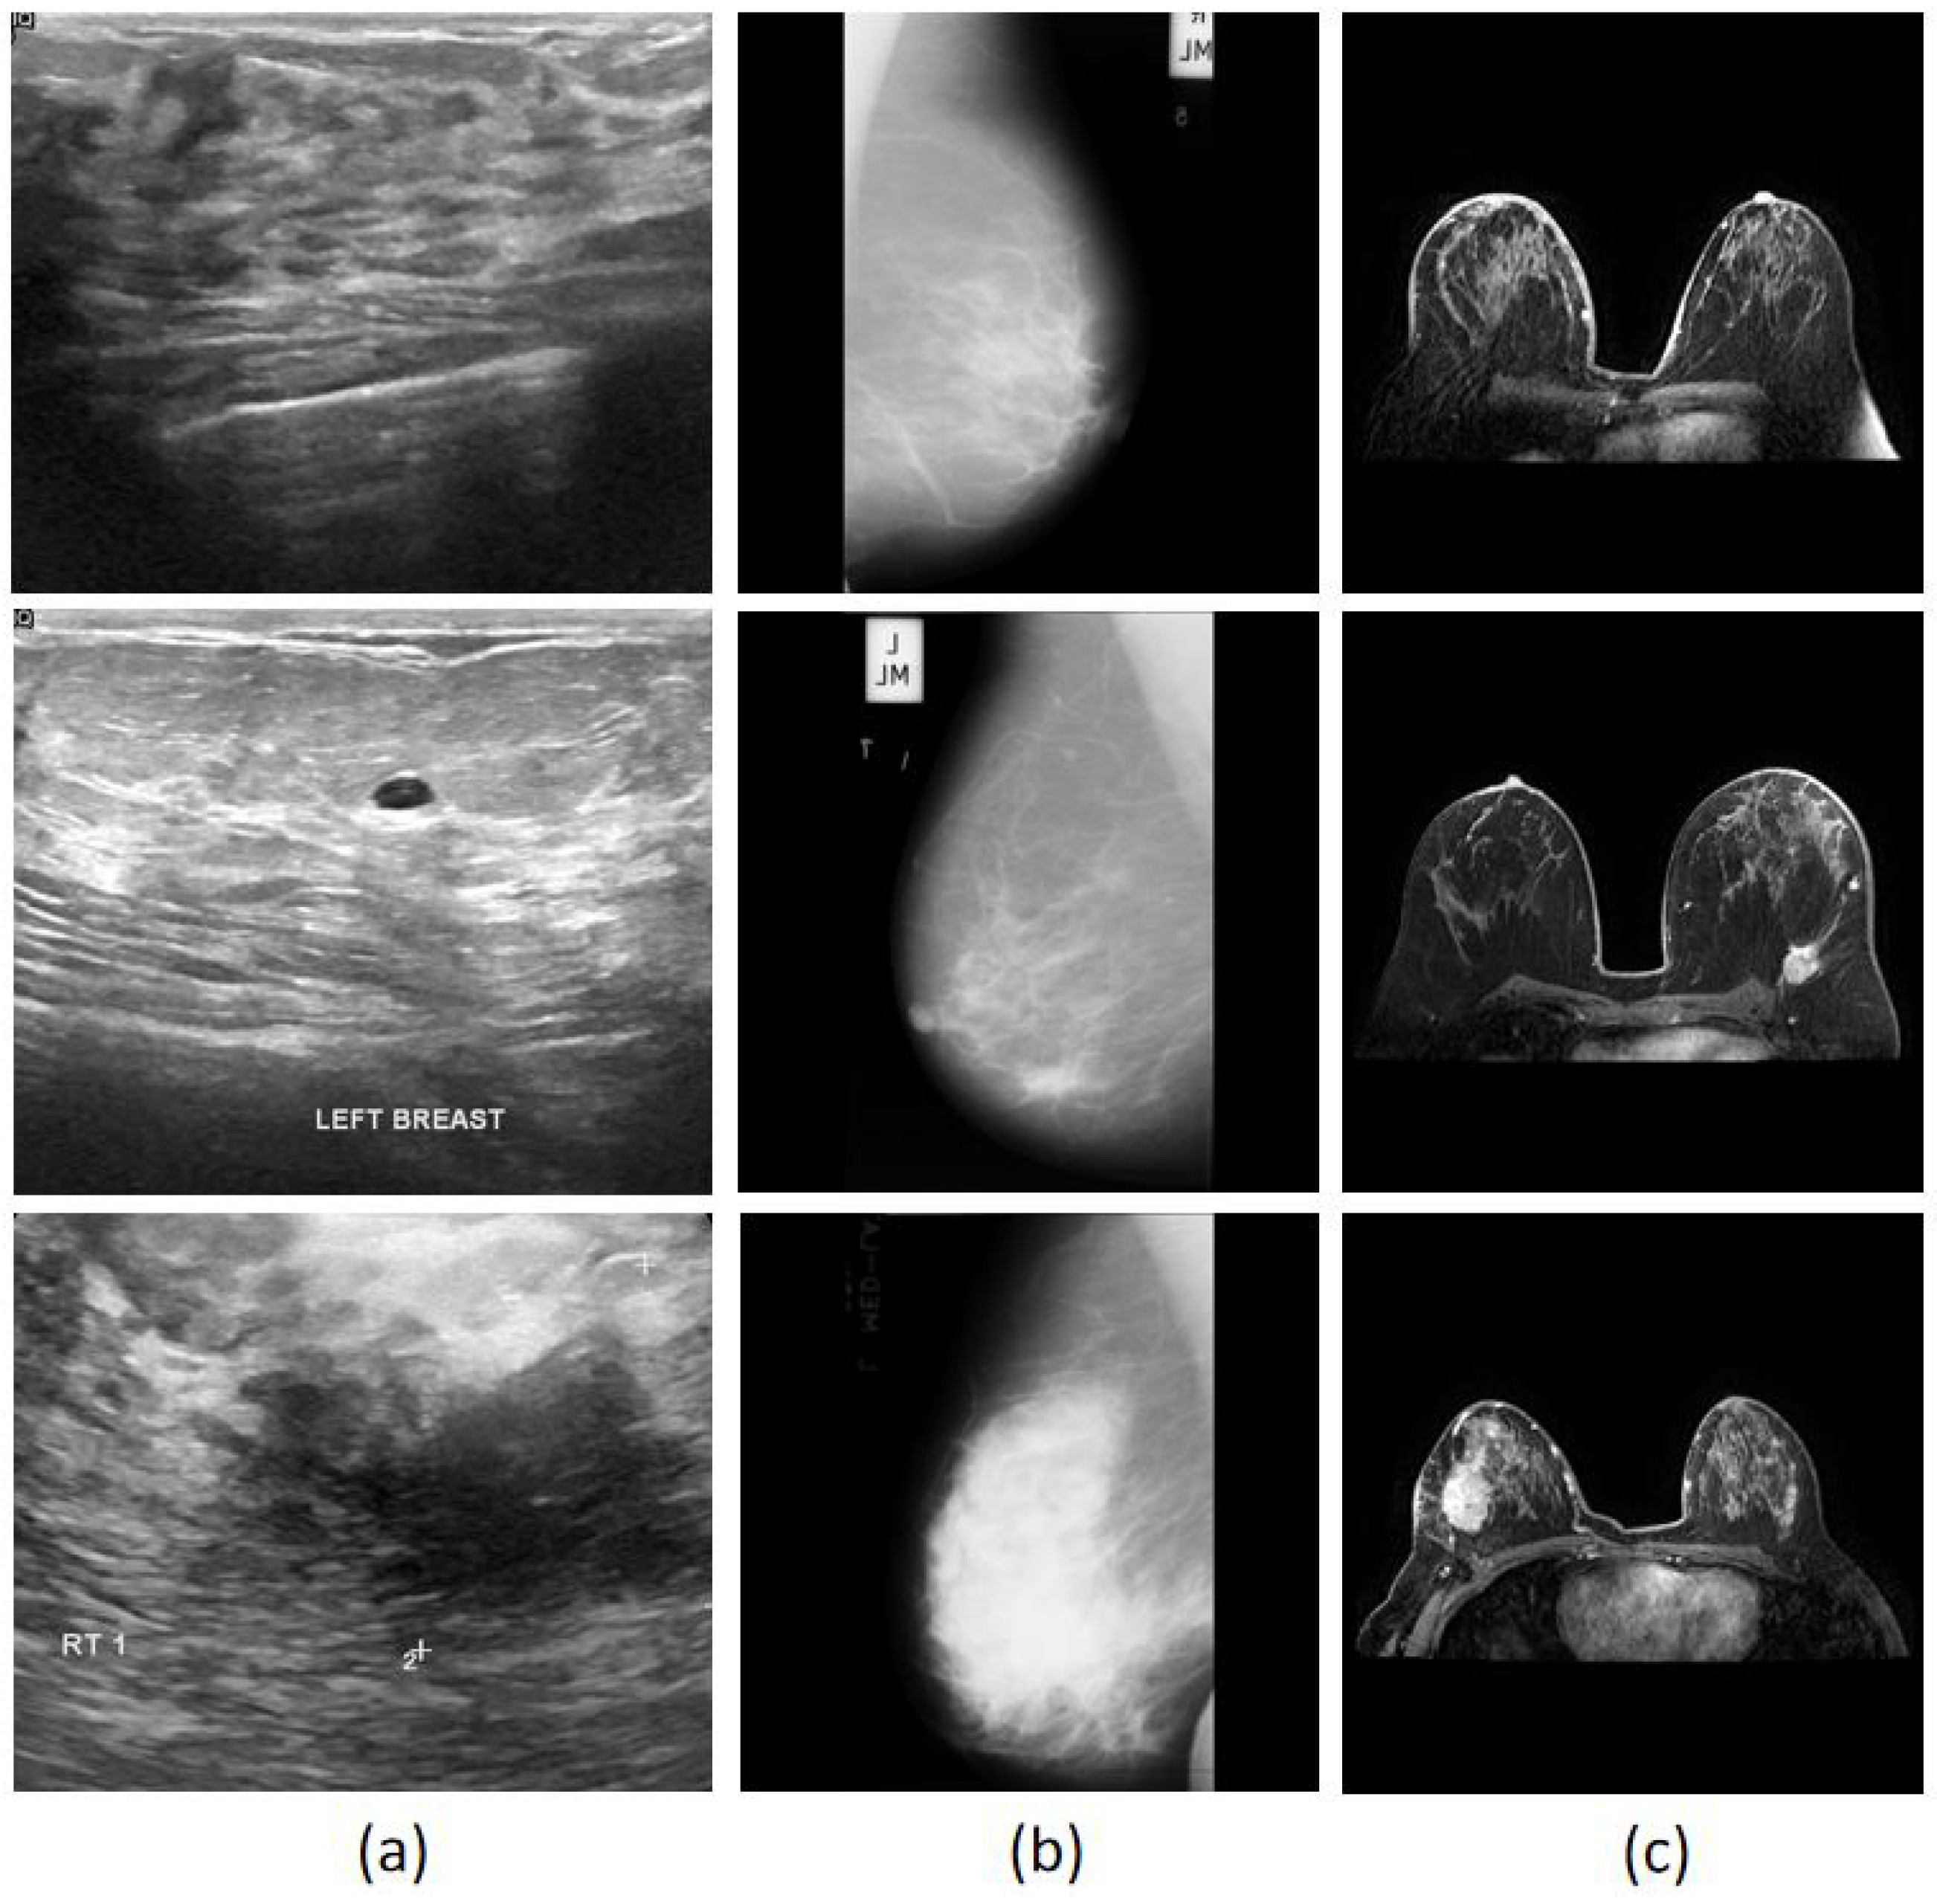

3.1. Data Collection

To validate the effectiveness of the CAD system in multiple breast imaging modalities, breast cancer data were collected from public datasets including ultrasound, mammography and MRI. The Breast Ultrasound Image (BUSI) dataset [36] contains a large number of breast ultrasound images categorised into normal, benign, and malignant classes. It contains a total of 780 grayscale images from 600 examples of women between the ages of 25 and 75. Each image is annotated by experienced radiologists, who provide high-quality tumour masks that clearly define the tumour boundaries. The Mammographic Image Analysis Society (MIAS) dataset [37] is a widely used resource in the field of mammographic image analysis, with a total of 322 mammographic images of classes of normal, benign and malignant. The resolution of all images is 1024 × 1024 pixels. Annotations are not provided in the dataset, but coordinates ( x , y ) of the lesion’s centre and its radius ( r ) in pixels are given in benign and malignant images. The Reference Image Database to Evaluate Therapy Response (RIDER) dataset [38] is a breast MRI dataset which that 1500 images of 5 patients. All images are 288 × 288 pixels and also contain ground truth tumour masks that were annotated by experts. Figure 6 depicts sample images of the collected datasets.

Figure 6. Sample images of breast cancer database. (a) Ultrasound BUSI; (b) mammography MIAS; (c) MRI RIDER.